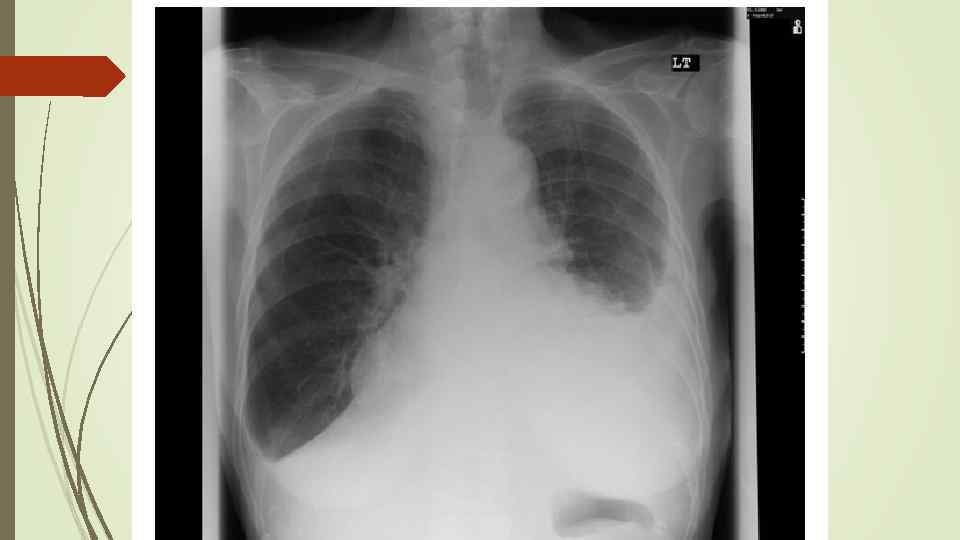

Плевральный выпот Скопление жидкости в плевральной полости (исключение гемоторакс, хилоторакс, пиоторакс) Транссудат Экссудат Плеврит

Плевральный выпот Скопление жидкости в плевральной полости (исключение гемоторакс, хилоторакс, пиоторакс) Транссудат Экссудат Плеврит

Осумкованные плевриты: а) пристеночные (паракостальные) осумкования, прилежащие широким основанием к поверхности ребер; б) верхушечные (апикальные) осумкования; в) диафрагмальные (базальные) осумкования, расположенные между основанием легкого и диафрагмой; г) междолевые (интерлобарные) осумкования, расположеные между долями легких; д) парамедиастинальные осумкования, расположенные в заворотах парамедиастинальной плевры.

Осумкованные плевриты: а) пристеночные (паракостальные) осумкования, прилежащие широким основанием к поверхности ребер; б) верхушечные (апикальные) осумкования; в) диафрагмальные (базальные) осумкования, расположенные между основанием легкого и диафрагмой; г) междолевые (интерлобарные) осумкования, расположеные между долями легких; д) парамедиастинальные осумкования, расположенные в заворотах парамедиастинальной плевры.